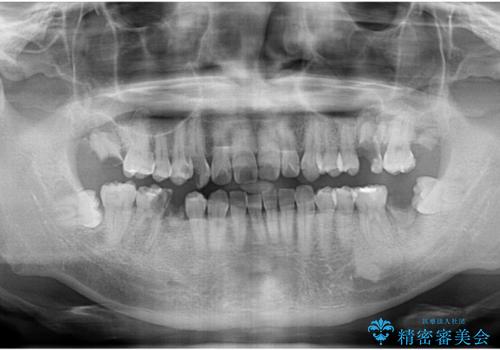

まず徹底的に虫歯を取り除き、保存が出来ない部位は抜歯(親知らずを含む)を行い、根管治療が必要な部位は精密根管治療を行いました。

その後、インプラント治療、セラミック治療を行いました。

一度治療するはを全て仮歯に変えて、歯茎を整えてからセラミックを装着しました。

また、虫歯が歯肉の中まである場合はAPF(歯肉弁根尖側移動術)も行なっています。